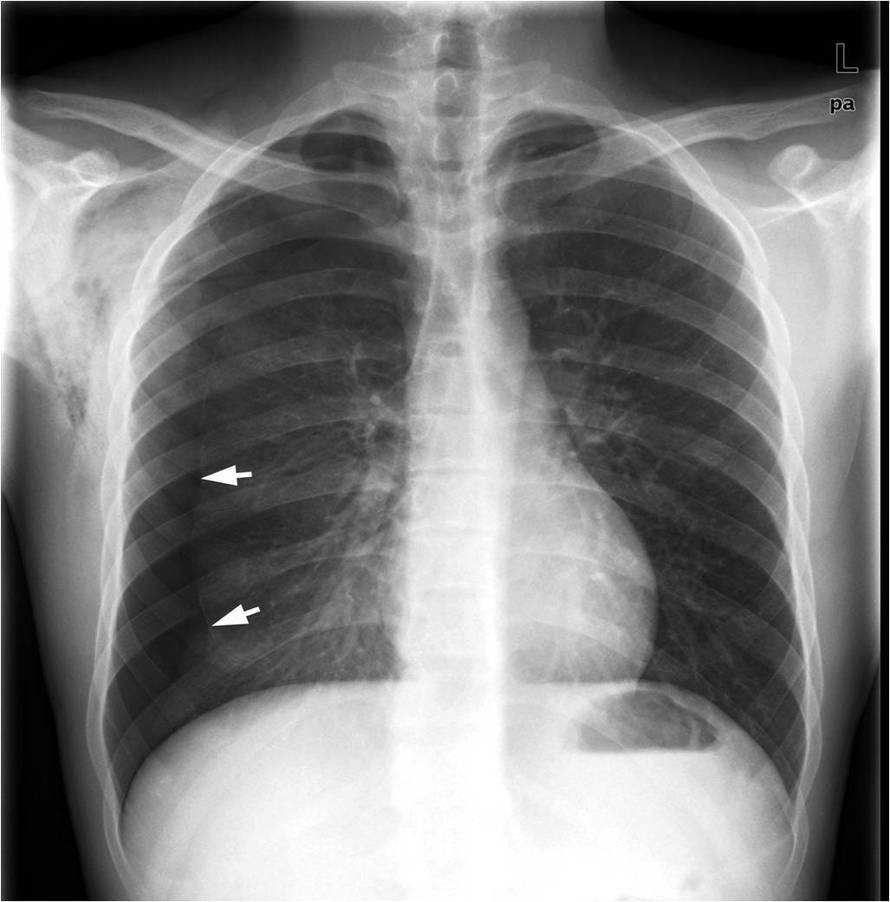

患者,男性,18岁,突发胸痛及呼吸困难2小时入院,急诊胸部DR摄片如图示,你的考虑是

A.肺大泡

B.肺气肿

C.气胸

D.胸腔积液

E.肺动脉栓塞